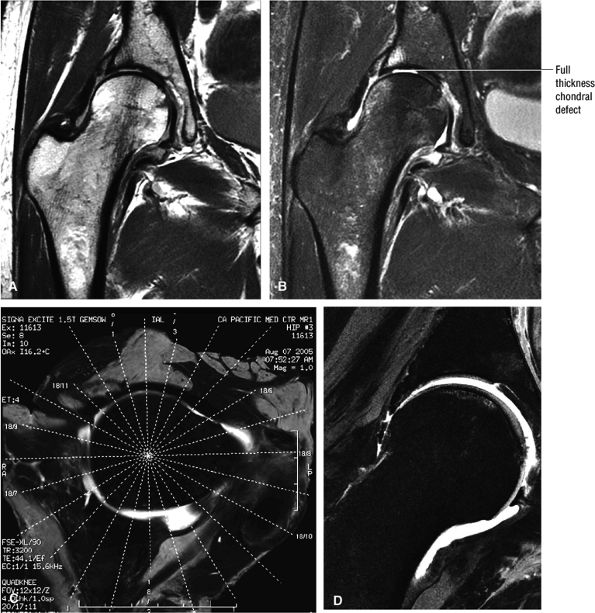

FIGURE 3.1 ● (A, B) Coronal plane images of the hip using a phased-array surface coil. Subtle acetabular sclerosis is identified on the coronal PD FSE image (A), and the full-thickness acetabular roof chondral defect is conspicuous on the FS PD FSE images (B and D). Although PD-weighted images are used more frequently than T1-weighted images, subchondral sclerosis is more apparent on T1-weighted contrast. (C) Radial image locations are prescribed from this FS PD FSE axial image centered on the femoral head. (D) High-resolution coronal FS PD FSE image (MR arthrogram) showing the potential to separate chondral surfaces of the acetabulum and femoral head.